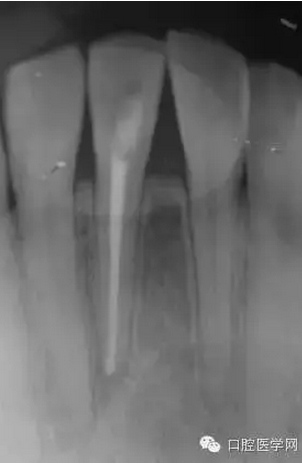

根管充填1個(gè)月后復(fù)診檢查過(guò)之后,一年后再次復(fù)診。如(圖5),可見(jiàn)大范圍破壞根尖周病變大部分基本治愈。

(圖 4) 根管充填1個(gè)月后

(圖 5) 根管充填約1年后